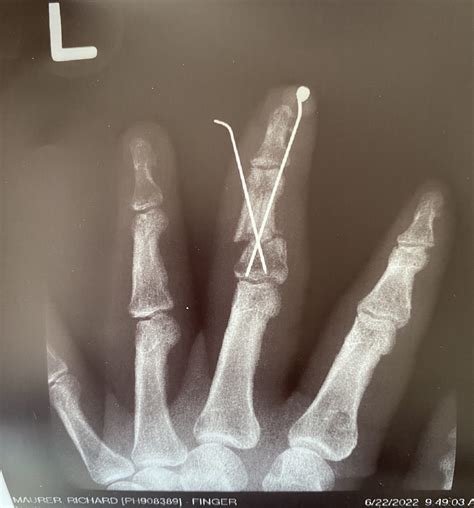

When you visit a doctor, they will perform a physical examination and almost certainly order an X-ray to confirm the location and severity of the fracture. Depending on the nature of the break, treatment plans may vary significantly.

• Surgery: In severe cases, particularly if the fracture involves the joint surface, is severely displaced, or is an unstable break, surgery might be required to insert pins, screws, or plates to hold the bone in place during the healing process.